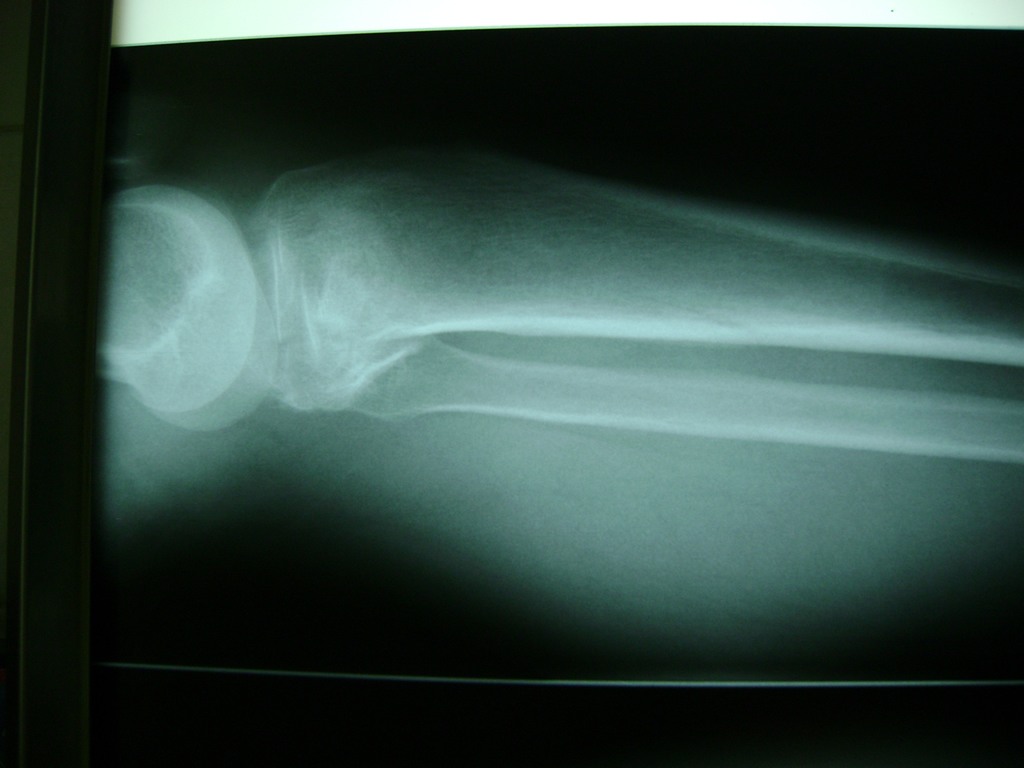

Cirugías de Húmero - Rodilla

La artroscopia de rodilla es un cirugía en el cual la estructura interna de la articulación es examinada ya sea para realizar un diagnostico o para realizar un tratamiento, este procedimiento se realiza utilizando un instrumento parecido a un pequeño tubo llamado artroscopio.